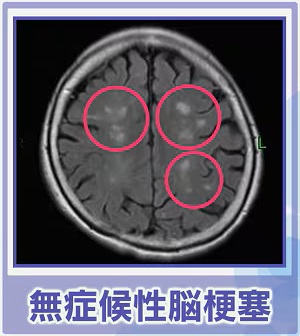

38108 B無念Nameとしあき25/11/02(日)22:39:26No.1363381751+ 10:21頃消えます

脳卒中スレ

交通事故の時に念の為MRI撮ったけど

40歳過ぎると誰でも隠れ脳梗塞の3つや4つはやってるんだとさ